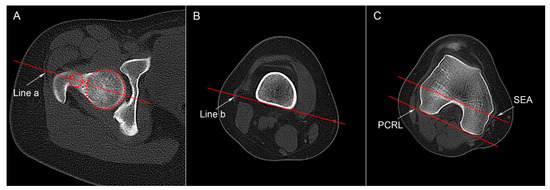

2.4.1. Femoral Anteversion